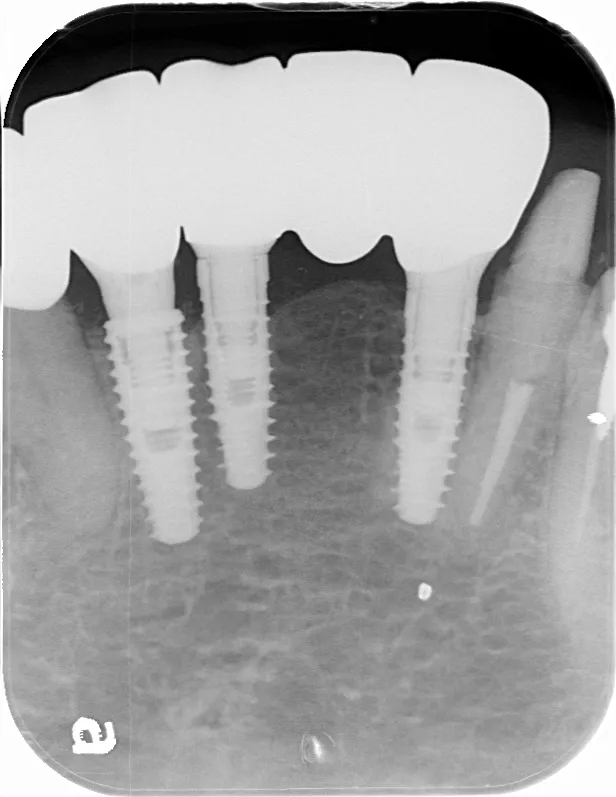

レントゲン画像